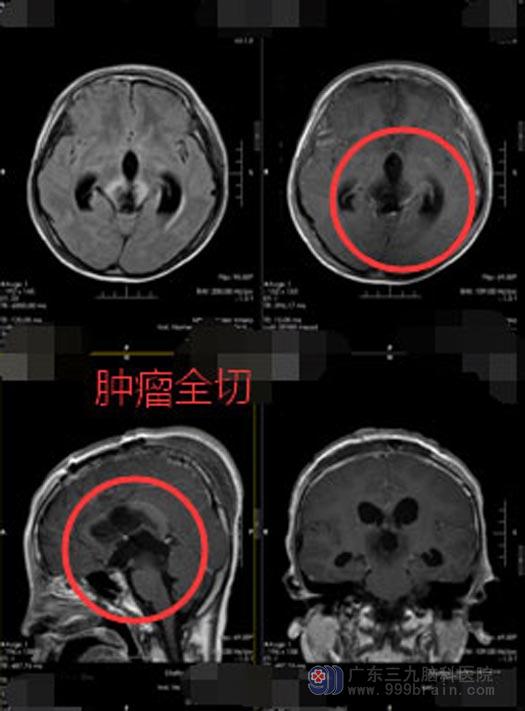

来到广东三九脑科医院神经外五科后,医院副院长、神经外五科主任建议小韩先放化疗再行手术。放化疗期间,小韩精神差,考虑和脑积水有关,急诊行‘脑室外引流术’。小韩术后精神好转,继续行放化疗。几天后他的病情再次加重,昏迷不醒。鲁明带领神经外五科医生团队立即给小韩行“右额纵裂-胼胝体-穹窿间入路行松果体区肿瘤切除术”,术中暴露肿瘤,见左侧视神经及颈内动脉被肿瘤压向前外方,与肿瘤粘连,明显变薄。分块切除肿瘤,肿瘤基底部起源于鞍膈,部分位于鞍上、部分位于鞍内,在显微镜下将肿瘤全切,视神经、视交叉、垂体、垂体柄等瘤周组织保护完好。

▲手术后